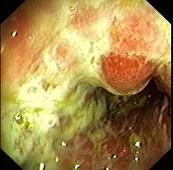

男性,68岁,腹痛1周,便血1天,既往有糖尿病和高血压病史。查体BP170/80mmHg,腹软,左下腹有压痛,无明显反跳痛,肠鸣音减弱。肠镜检查图片如下,...

问题 男性,68岁,腹痛1周,便血1天,既往有糖尿病和高血压病史。查体BP170/80mmHg,腹软,左下腹有压痛,无明显反跳痛,肠鸣音减弱。肠镜检查图片如下,最可能的诊断是 ( )

选项 A、Crohn病 B、肠结核 C、大肠癌 D、溃疡性结肠炎 E、缺血性结肠炎

答案 E